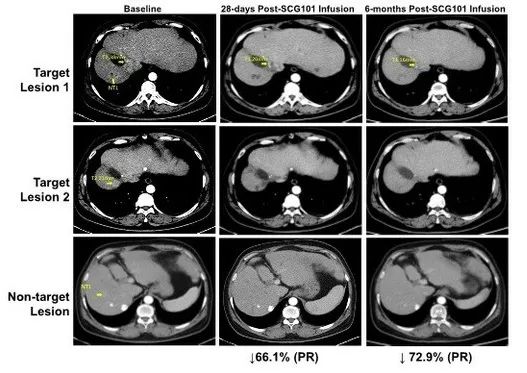

一项关于“SCG101治疗乙型肝炎病毒(HBV)相关肝细胞癌(HCC)”的临床研究,共纳入1例HBV相关的肝细胞癌患者,入组后仅接受单剂SCG101输注,而未接受其他抗肿瘤治疗,结果显示如下:

1、肿瘤缓解:患者在治疗第28天,达到部分缓解(PR),肿瘤靶病灶相比基线缩小66%,并在治疗第4个月进一步缩小至74.5%;同时另一处病灶完全消失。截至数据统计时,该患者肿瘤未进展时间已超过6.9个月。

图2 HBV相关肝细胞癌患者,回输SCG101前后影像学变化

▲图源“CISION”,版权归原作者所有,如无意中侵犯了知识产权,请联系我们删除

2、HBV感染缓解:该患者在回输SCG101前后,肝脏免疫组化结果显示,乙肝表面抗原阳性肝细胞达到100%清除;HBsAg(HBV血清学标志)水平,也从治疗前的557.96 IU/mL,下降至1.3 IU/mL(回输SCG101第7天)、0.08 IU/mL(回输第28天)。